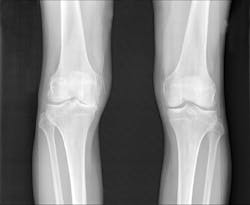

"The imaging tests most frequently used, x-rays, don't indicate the level of pain or allow us to directly see the amount of cartilage loss, which is a challenge for physicians and patients," says Averi A. Leahy, BA, an MD/PhD student in the medical scientist training program at TUSM and the Sackler School. "The fluorescent probe made it easy to see the activities that lead to cartilage breakdown in the initial and moderate stages," says Shadi A. Esfahani, MD, MPH, postdoctoral fellow in the division of nuclear medicine and molecular imaging at Massachusetts General Hospital, and in the department of radiology at Harvard Medical School.